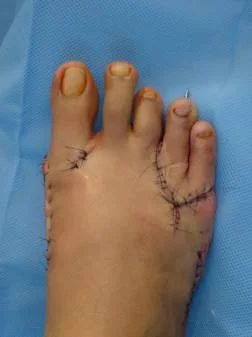

Hallux valgus. Caso clínico:

Paciente femenino de 32 años de edad, quien consulto por dolor en pie derecho, secundario a hallux valgus por metatarso primo varo. Fue intervenida quirúrgicamente con excelentes resultados. Ver más.